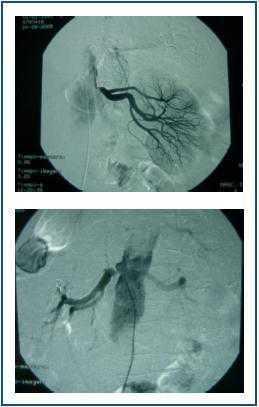

The arteriography detected stenosis in both renal arteries (figure 1), which was corrected with angioplasty and stent.

Figure 1.